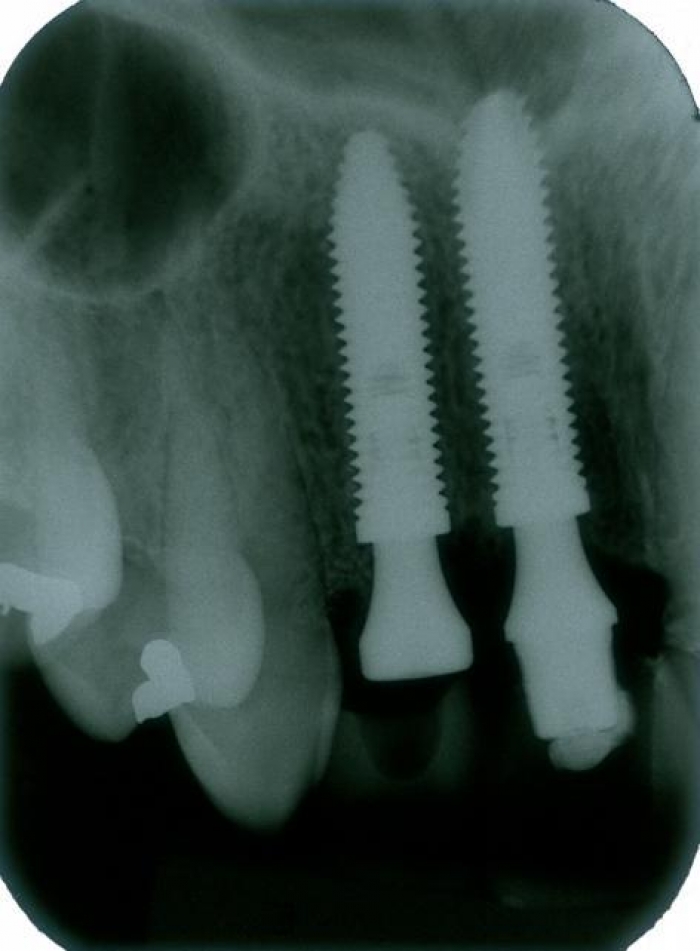

Rx dos implantes Cone Morse instalados

Raio X final